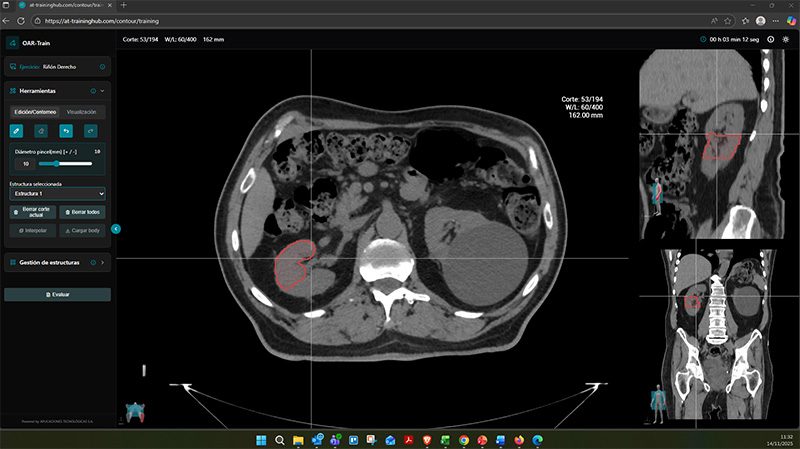

Lo ha logrado al desarrollar la primera herramienta formativa en línea para practicar el contorneo de órganos de riesgo, que permite al personal sanitario en formación practicar en un entorno seguro la delimitación de órganos de riesgo (OAR) en pacientes oncológicos, una tarea crítica en radioterapia donde cada milímetro marca la diferencia entre preservar un órgano sano o comprometer la eficacia del tratamiento. Con casos reales, retroalimentación experta y un sistema de comparación con resultados de especialistas que facilita el aprendizaje autónomo, la repetición flexible y el perfeccionamiento continuo.

OAR-Train nace precisamente para acercar la práctica real al aula. Un conjunto amplio y significativo de casos clínicos reales, bien documentados y preparados con el aval de expertos, se pone a disposición de docentes y estudiantes para abordar la correcta delimitación de órganos de riesgo en la planificación de tratamientos de radioterapia. Este aspecto es clave, y, gracias a OAR-Train, puede trabajarse con una herramienta realista, accesible y respaldada por instituciones de prestigio.

OAR-Train encarna muy bien lo que entendemos por innovación educativa aplicada: combina investigación clínica, ingeniería biomédica y tecnología con un objetivo claro de mejorar la formación y la práctica sanitaria. Permite entrenar una habilidad crítica en radioterapia, como es el contorneo preciso órganos de riesgo, y eso tiene un impacto directo en la calidad del tratamiento y en la seguridad del paciente. Al final, mejora la formación de los profesionales y refuerza el propio sistema sanitario.